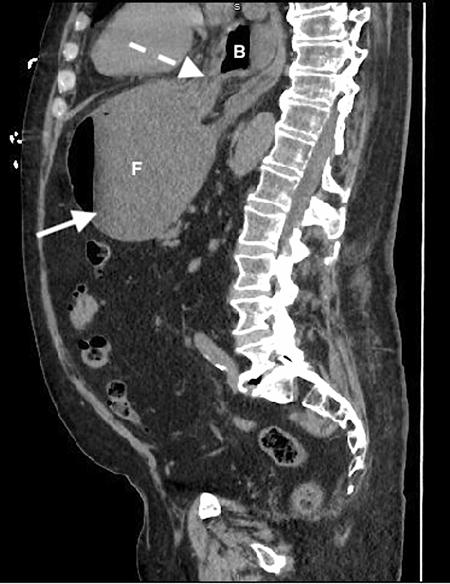

加急CT检查显示中至大型食管裂孔疝和由于胃扭转而呈现的胃部水肿膨胀并伴有部分梗阻(图3-5)。

(图3)

(图4)

(图5)

当怀疑有胃扭转时,选择初始的影像学检查非常重要,因为诊断延迟可能导致致命的并发症。CT检查高度可靠,主要有两种表现,即正常的胃窦幽门移行区和胃窦位置异常,诊断急性胃扭转的敏感性和特异性均为100%。POCUS是一种有效的非侵入性影像检查方式,主要用于床旁评估。此外,POCUS无辐射,并可根据临床情况随时进行重复检查。本例患者POCUS检查显示,胃部严重扩张,胃内容物分层,类似胃出口梗阻(GOO)的“黑白饼干”征象。POCUS还可以用来动态观察胃减压成功与否。